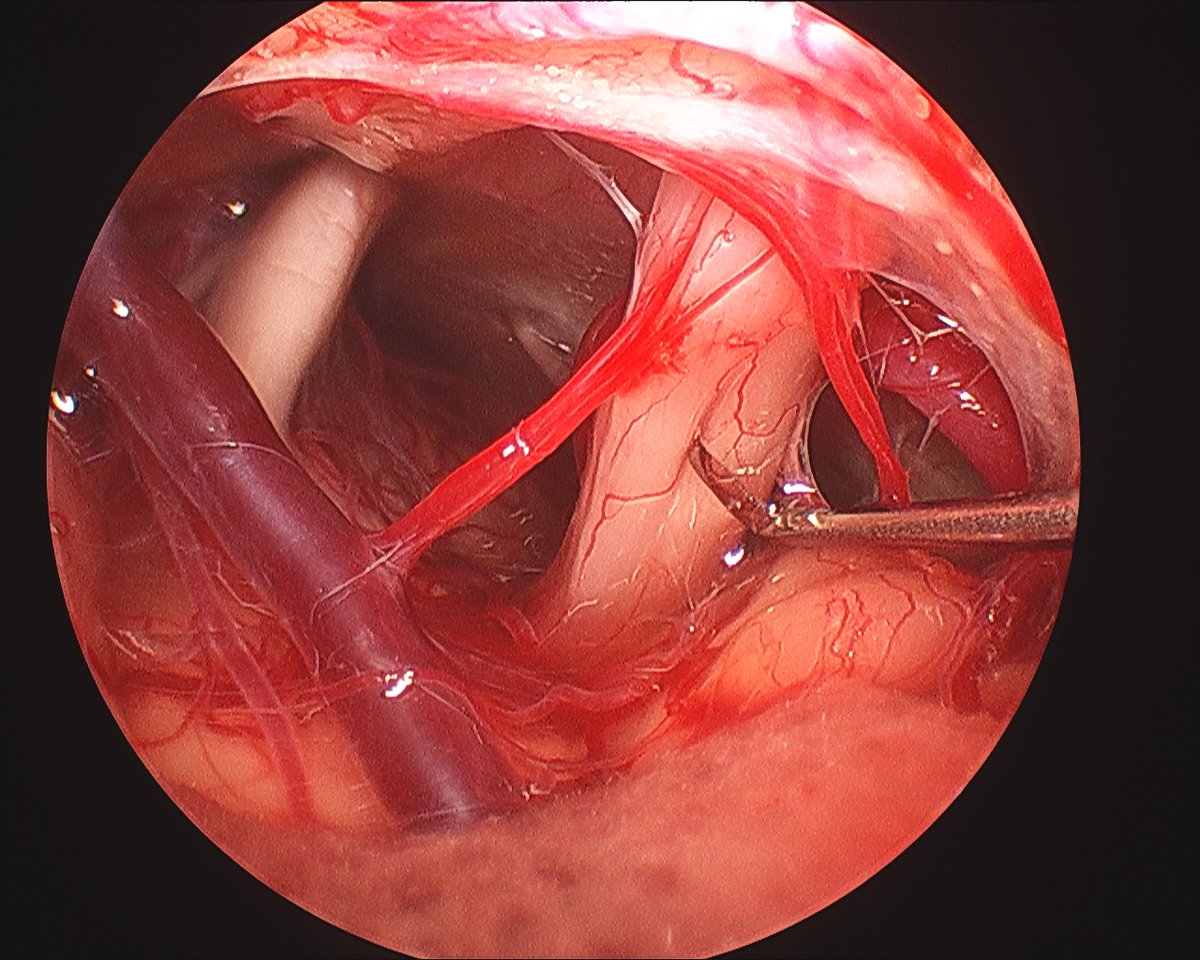

“Peel off” modification of the technique of anterior rerouting of facial nerve in the infratemporal approach type A. Presented by Martin Chovanec, MD.

@ceorlhns2019#otology#otosurgery pic.twitter.com/QukGfTrrQa – mjesto: Square Brussels Meeting Centre -

Right cisternal cranial nerve 8

#anatomy. The vestibular nerves (sup/inf) run superior (left) to the cochlear nerve. Different orientation than in IAC. The plane between the nerves can be teased out and is often marked by a small artery.#skullbase#nsgy#otology@HouseInstitutepic.twitter.com/zFsCT1WCHN